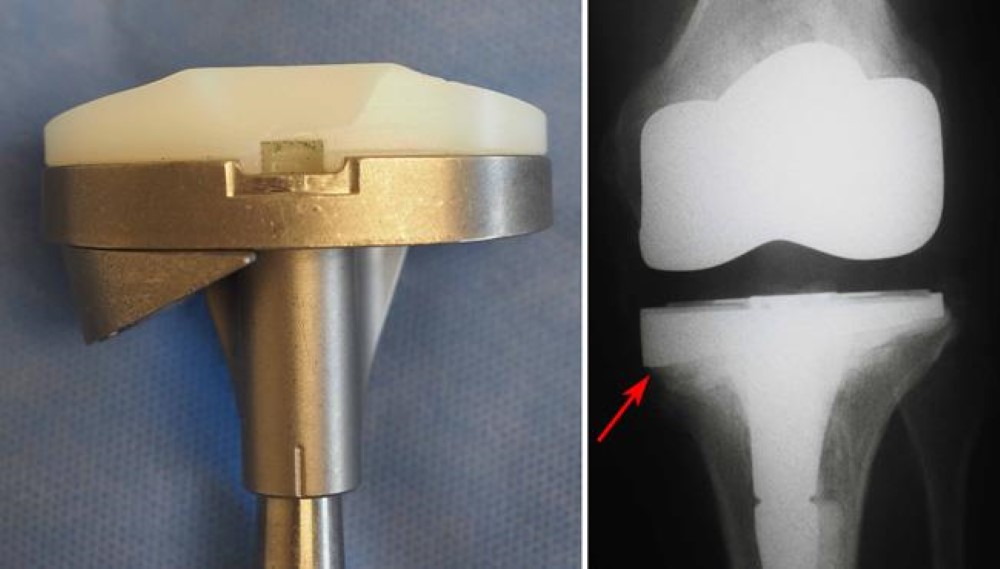

metal augments for knee implants

Examples of metal augments that can be added to implants to make up for lost bone.

additional block added to knee implant

(Left) In this tibial component, an additional block has been attached to make up for lost bone. (Right) An X-ray of the augmented component in place within the knee.

Photo and image courtesy of Stuart J. Fischer, MD, FAAOS